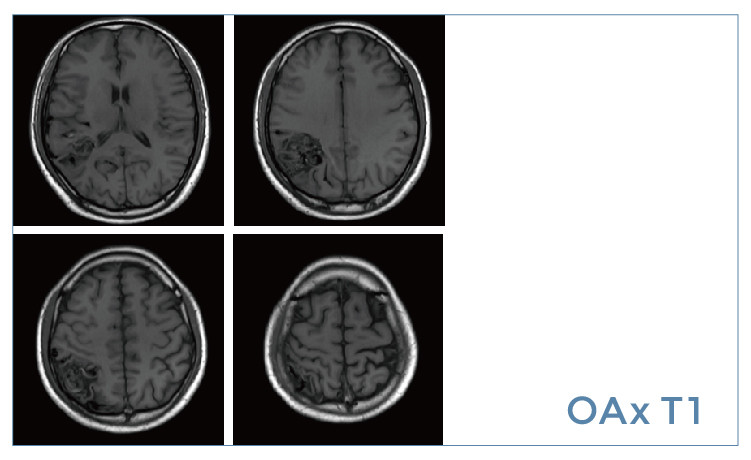

【朗润影像档案】20190531磁共振影像病例结果讨论